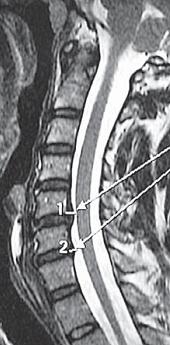

На МРТ № 17 наблюдается вентральная грыжа межпозвонкового диска в сегменте ThXII-LI с выраженными спаечными процессами на этом уровне, с вовлечением в данный процесс брюшной аорты В сагиттальной плоскости (вертикальный срез) грыжи межпозвонковых дисков разделяют на вентральные, дорсальные, краниальные и каудальные. МРТ № 18